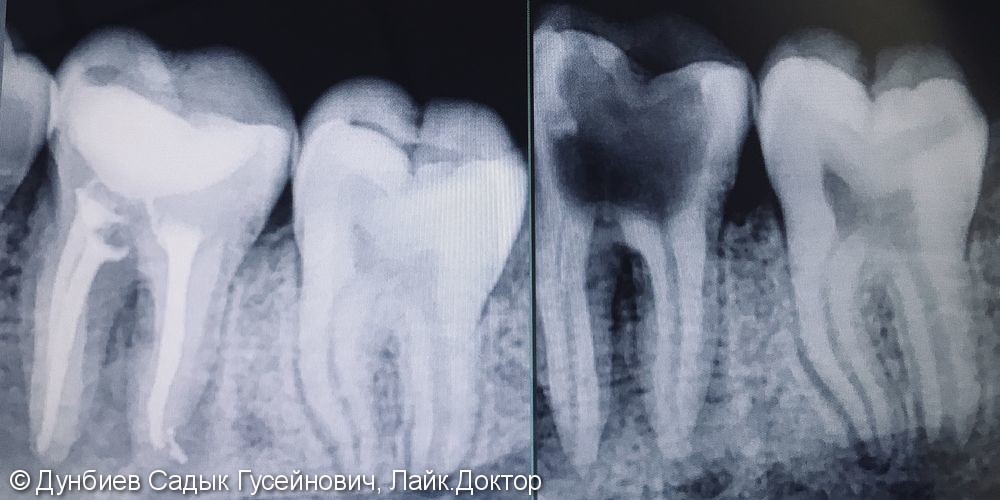

Рентгеновские снимки кариеса корня зуба

Раздел: Визуальные уроки